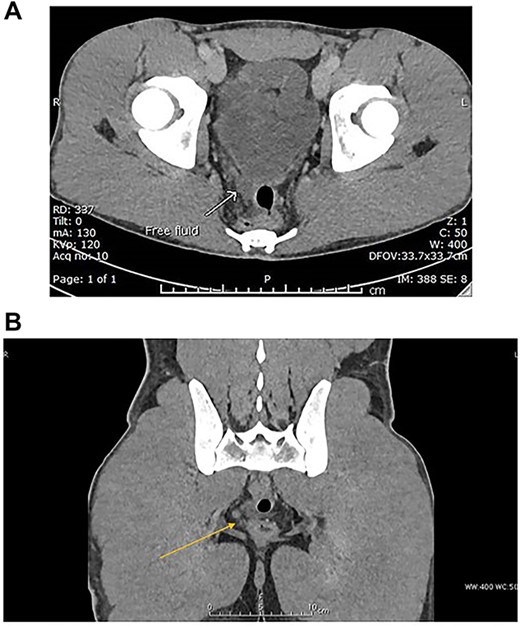

Abdominal CT with intravenous (IV) contrast (Fig. 2A and B) revealed:

(A) Coronal CT scan section: arrow indicates free fluid in the Douglas pouch. (B) Axial CT scan section: arrow indicates free fluid in the Douglas pouch.

No solid abdominal organ injuries.

Mild free fluid was noted in the pelvis.

No abnormal bowel enhancement or bowel dilatation.

No free air in the abdomen.

The bones were intact.